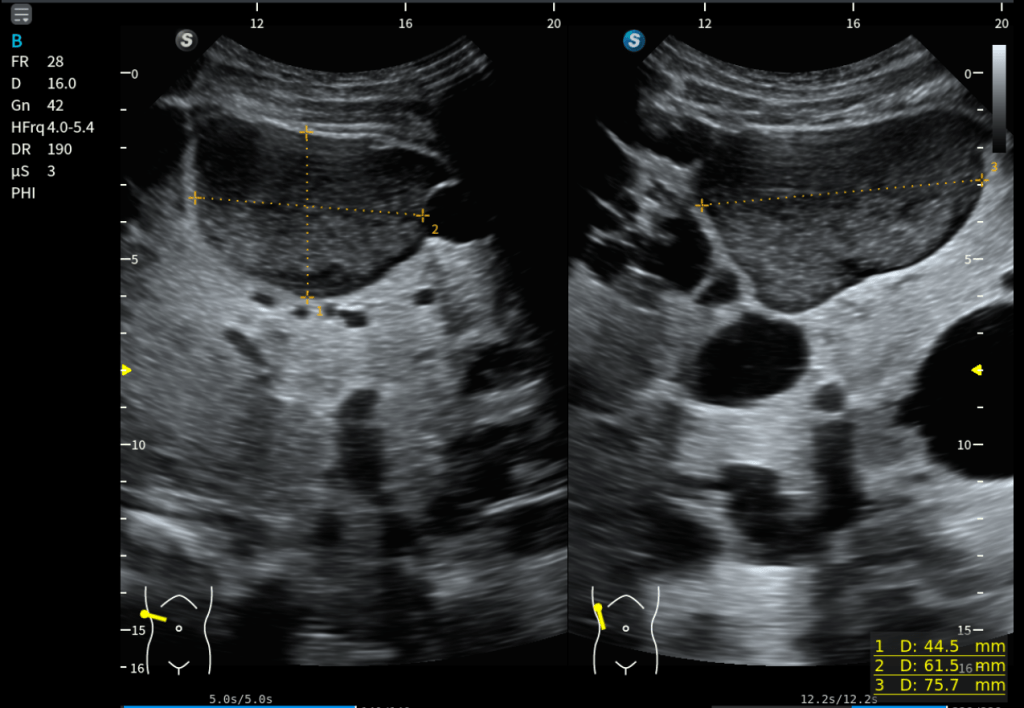

El detalle fino: la aportación de la sonda lineal

Como parte del protocolo ecográfico, además de la sonda convex se realizó exploración con sonda lineal de alta frecuencia, especialmente útil en hígado superficial.

Aquí apareció un hallazgo muy interesante:

- Múltiples lesiones hiperecogénicas redondeadas

- Distribuidas por el parénquima hepático

- Coexistiendo con los quistes hepáticos

Fue un hallazgo casual, pero muy bien demostrado en la última imagen del estudio. Esta coexistencia entre lesiones quísticas y lesiones sólidas hiperecogénicas no había quedado inicialmente descritas y pone en valor la importancia de complementar la exploración.